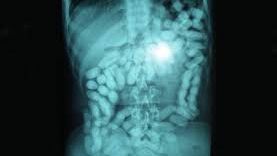

Odată ajunşi în Madrid, românii însoţiţi de şeful bandei erau transportaţi cu o furgonetă în Cadiz de unde plecau spre Maroc. Aici, drogurile, în principal haşiş, erau înfăşurate în latex şi apoi înghiţite de traficanţi, pachetele fiind „extrase” la întoarcerea în Spania.